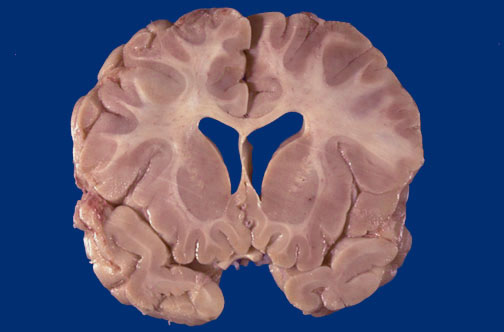

Identify the following regions of the normal brain in the image above: Caudate Nucleus - Putamen - Corpus Callosum - Septum Pellucidum - Optic Nerve & Chiasm - Lateral ventricle - Temporal lobe